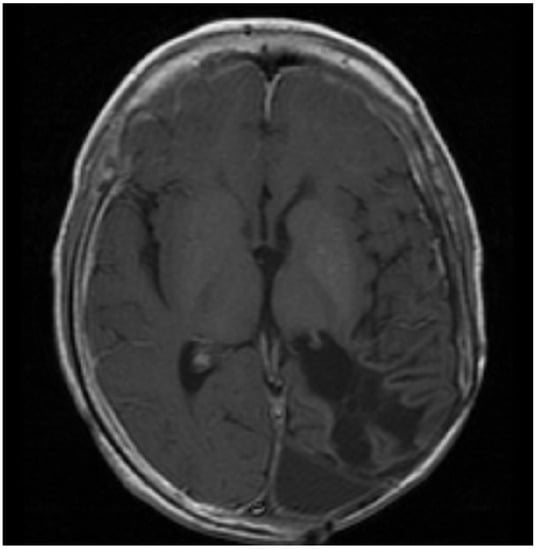

Figure 2.

Patient 2: MRI shows confluent encephalomalacia gliosis in the left temporal and occipital lobes. There was no evidence of mass or pathologic enhancement 8 years from diagnosis and 4 years off therapy.